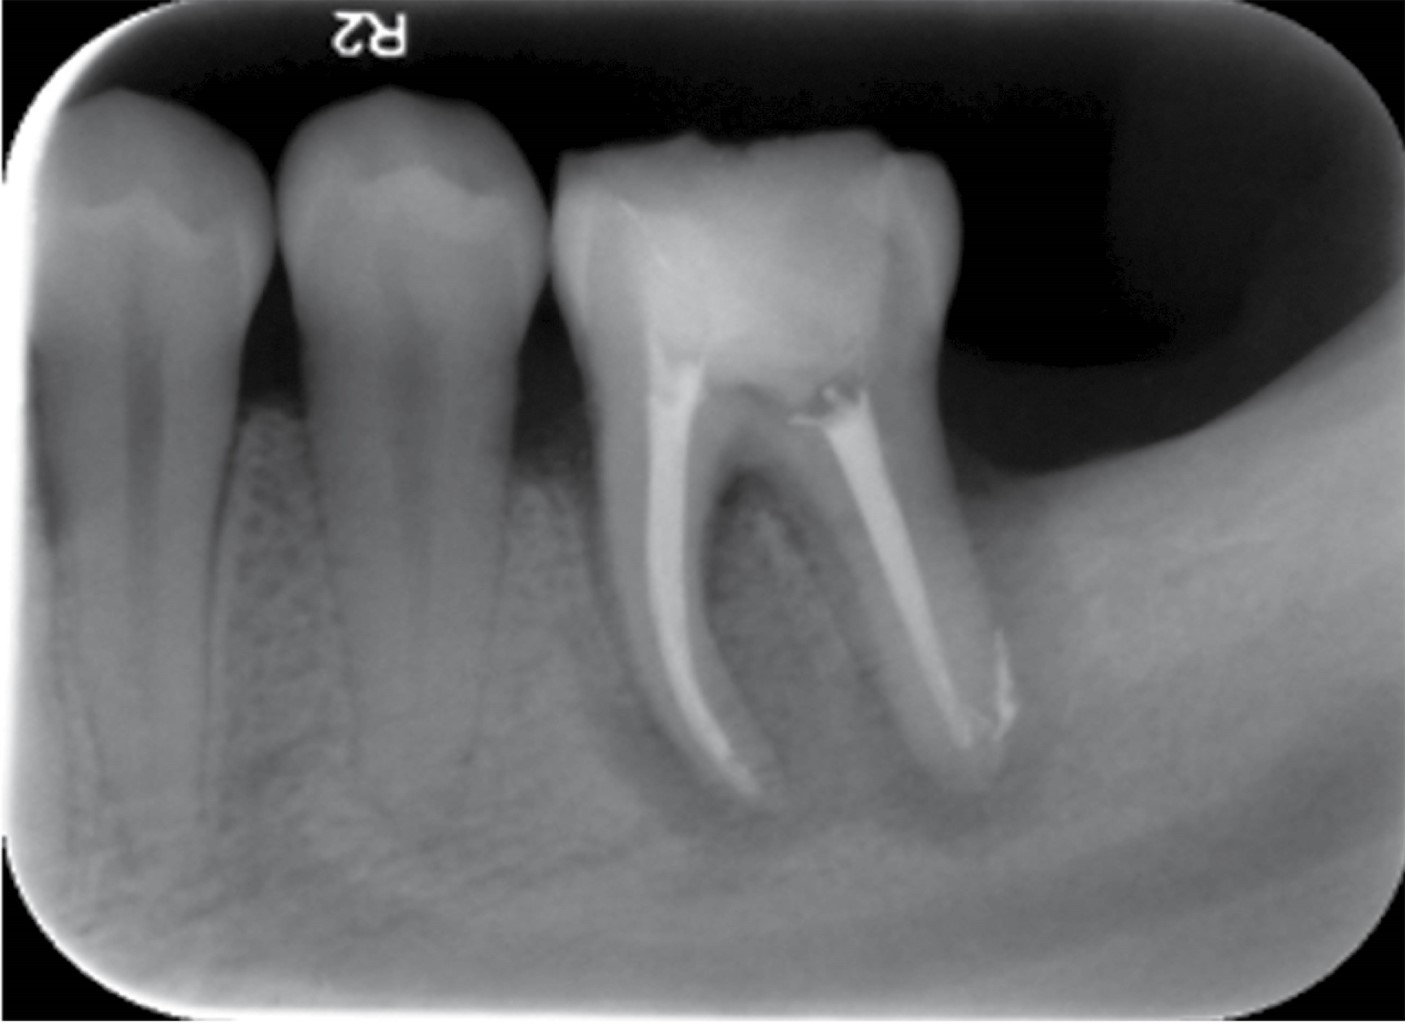

Figure 4